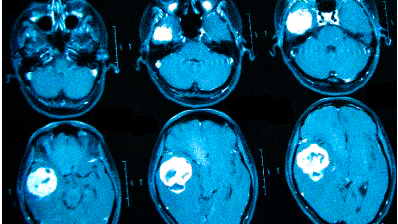

Выделяют несколько видов магнитно-резонансной томографии головы: нативную, усиленную контрастным препаратом и сканирование в ангиорежиме. К каждому исследованию есть свои показания, поэтому ответить на вопрос: “Какую МРТ делать при головной боли?” — не всегда возможно. Врач выбирает нужный тип диагностики, опираясь на клиническую картину. В оценке опухолевых новообразований и для определения стадийности (в том числе — метастатического распространения) используют МРТ с контрастированием. Введение препаратов на основе хелатов гадолиния позволяет рассмотреть даже небольшие опухоли в труднодоступных местах, поэтому магнитное сканирование с усилением с успехом применяют, если прочие способы визуализации показали неоднозначные результаты. При подозрении на сосудистое заболевание головного мозга оптимальным выбором будет проведение сканирования в ангиорежиме.

Онкологи считают, что при нарастающих головных болях с прочими необъяснимыми симптомами (обмороками, ухудшением памяти, выпадением полей зрения, давлением на глазные яблоки и др.) в первую очередь следует исключить опухолевую патологию

Частые головные боли вызывают разные причины. Иногда так проявляется серьезное заболевание. В 90% случаев после определения генеза возможно адекватное лечение, которое улучшит качество жизни. Состояния, для которых типична цефалгия::

опухоли;